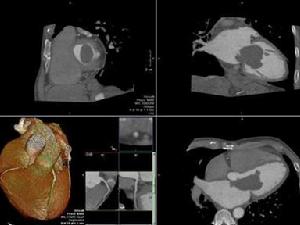

粘液瘤病例多無風濕熱病史,病程較短,症狀和體徵可能隨體位變動而改變。心電圖大多顯示竇性心律。超聲心動圖檢查可以看到粘液瘤呈現的能移動的雲霧狀光團回聲波。左心房粘液瘤在收縮期時光團位於心房腔內,舒張期時移位到二尖瓣瓣口。超聲心動圖檢查診斷準確率極高。